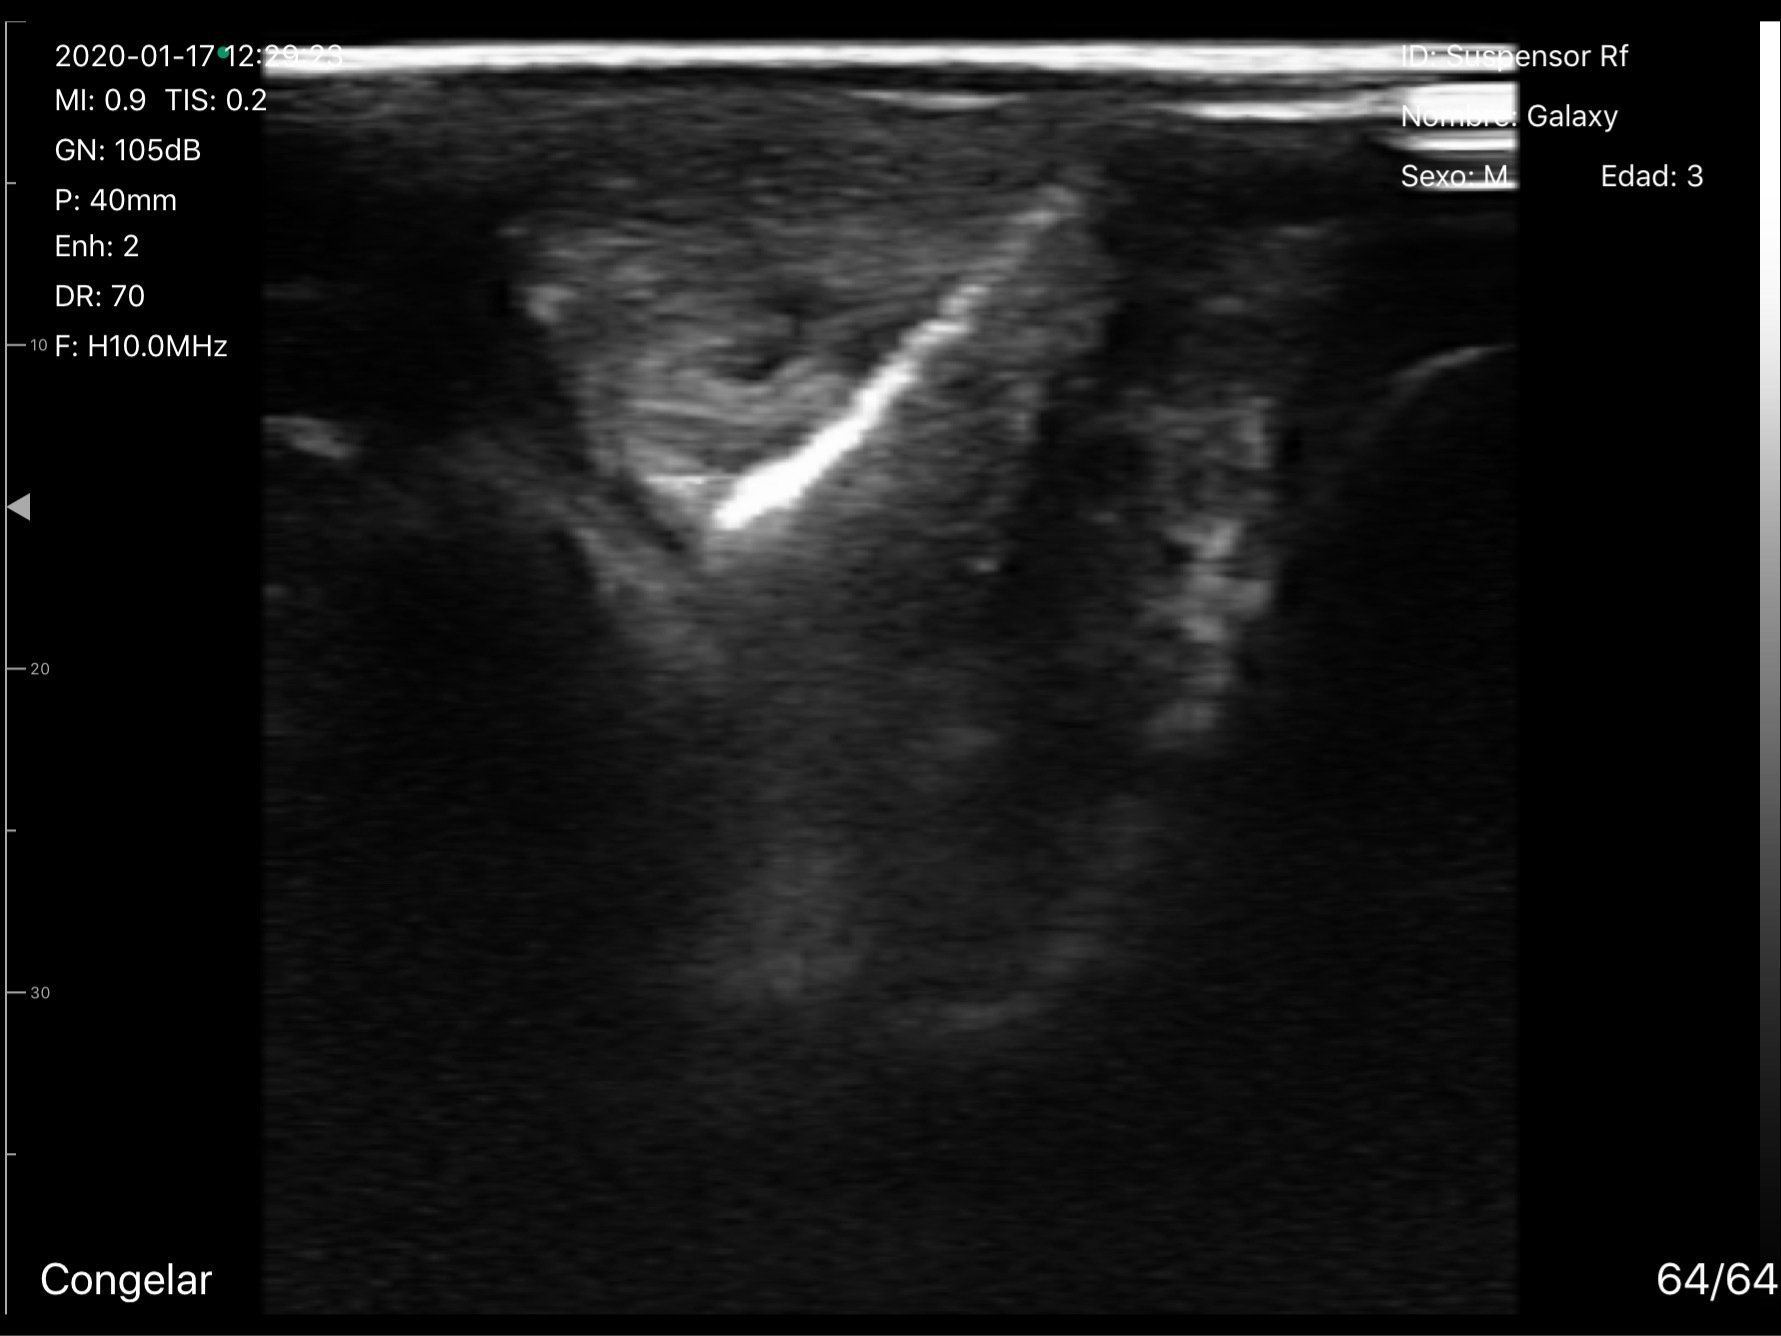

Electrólisis percutanea

La electrólisis percutánea es un novedoso tratamiento para tendinosis que consiste en la aplicación ecoguiada de una corriente eléctrica en la zona de la lesión. Este tratamiento se puede combinar con ultrasonido terapéutico o Indiba y es muy útil en problemas crónicos.